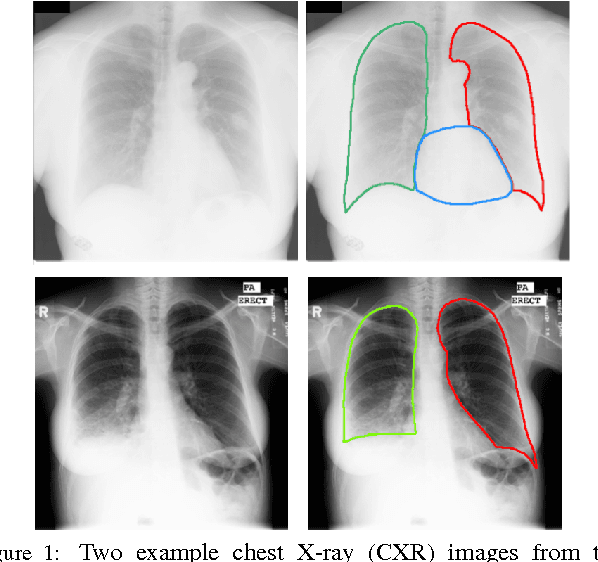

Abstract:Chest X-ray (CXR) is one of the most commonly prescribed medical imaging procedures, often with over 2-10x more scans than other imaging modalities such as MRI, CT scan, and PET scans. These voluminous CXR scans place significant workloads on radiologists and medical practitioners. Organ segmentation is a crucial step to obtain effective computer-aided detection on CXR. In this work, we propose Structure Correcting Adversarial Network (SCAN) to segment lung fields and the heart in CXR images. SCAN incorporates a critic network to impose on the convolutional segmentation network the structural regularities emerging from human physiology. During training, the critic network learns to discriminate between the ground truth organ annotations from the masks synthesized by the segmentation network. Through this adversarial process the critic network learns the higher order structures and guides the segmentation model to achieve realistic segmentation outcomes. Extensive experiments show that our method produces highly accurate and natural segmentation. Using only very limited training data available, our model reaches human-level performance without relying on any existing trained model or dataset. Our method also generalizes well to CXR images from a different patient population and disease profiles, surpassing the current state-of-the-art.